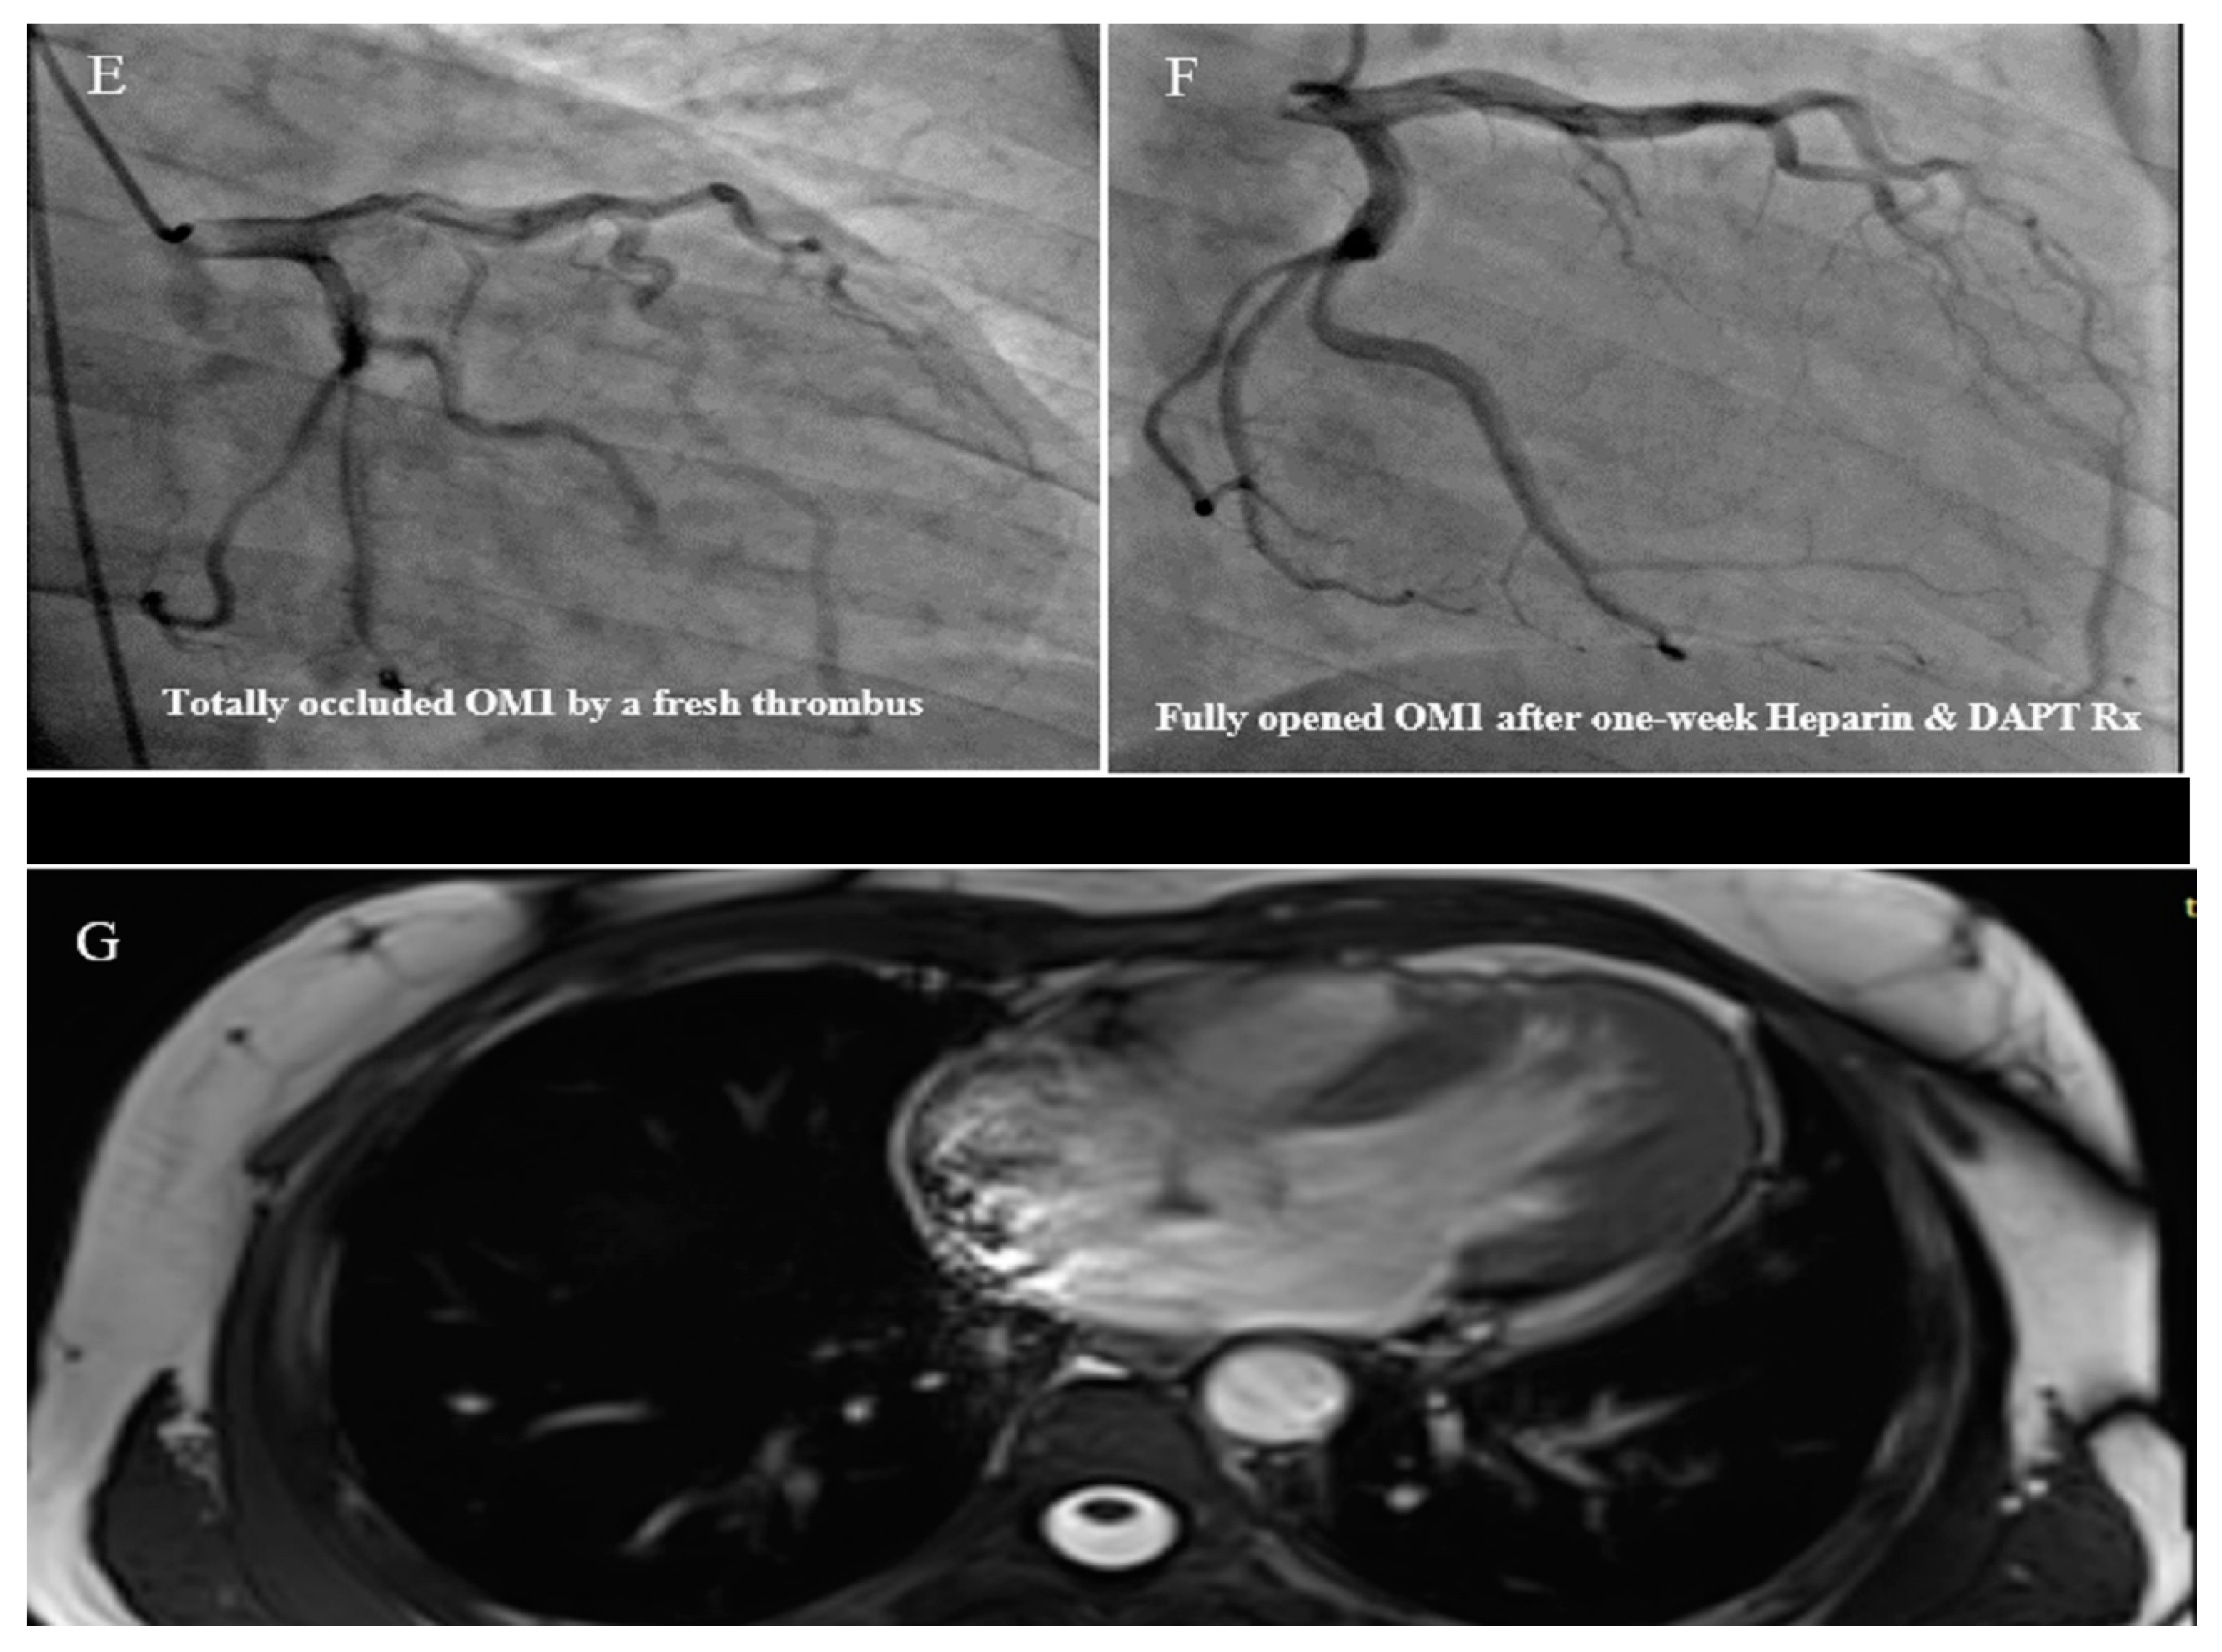

2.11. Case #11. NCLV, BAV, and Old Myocardial Infarction

| 11 | F | 62 | Echocardiography before diagnostic angiography | Old MI, DM, HLP | NCLV, LVEF = 34% | BAV | − | − | Indicated for CABG according to the result of coronary angiography, she refused and left the hospital | Did not refer again to our center |